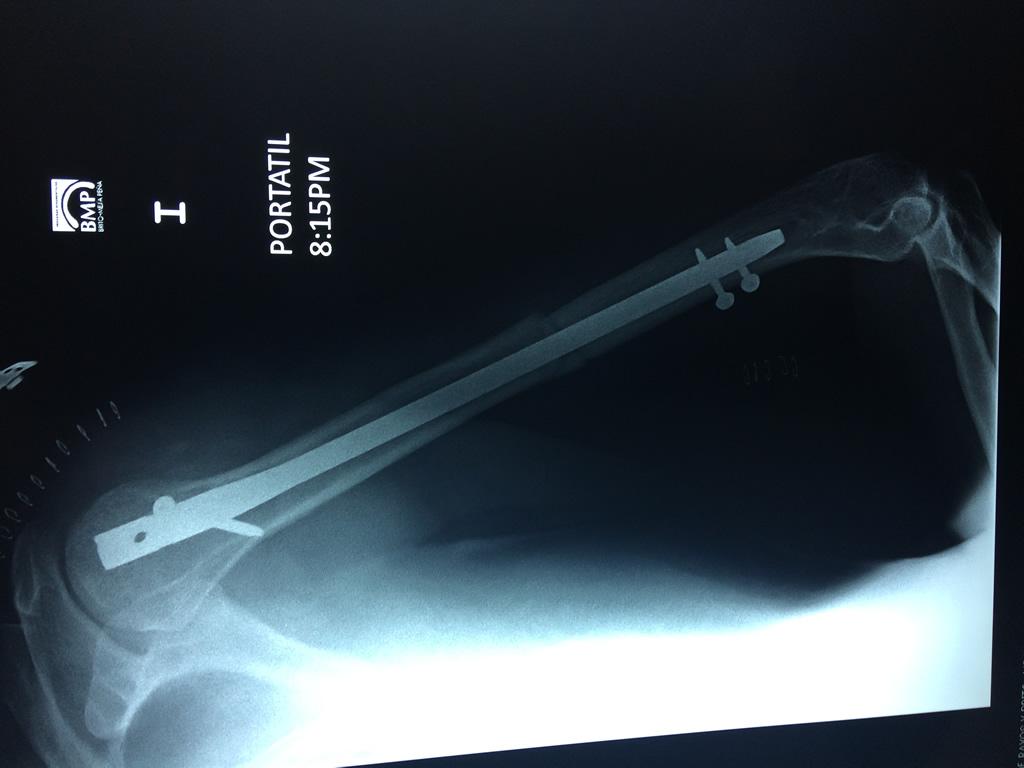

Cirugía de Fémur - Húmero

El Húmero (en latín, humerus) es el hueso más largo de las extremidades superiores en el ser humano. Forma parte del esqueleto apendicular superior y está ubicado en la región del brazo. ... El extremo proximal del húmero tiene la cabeza, cuellos quirúrgico y anatómico y tubérculos mayor y menor.